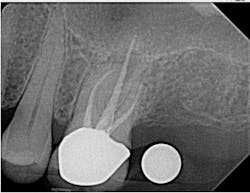

As my implant experience grows, I find myself ordering CBCT-based surgical guides more often. When used properly, a guide can make the procedure shorter, safer, and less stressful for both the doctor and the patient. I am a firm believer in placing screw-retained restorations whenever possible; preplanning my surgery with a digital wax-up and using a surgical guide ensures that the implant is in the optimum restorative position (figures 4–5). Even though an experienced surgeon with top-notch clinical skills can place an implant in an acceptable position most of the time, there is no way they can place it in a better position than with a surgical guide. They can only hope to do as well—not better.

I also use my ProMax 3D Classic for endodontic evaluation and treatment when needed (figures 6–8). A small field of view (5 cm x 5 cm) image can be taken to limit radiation exposure and focus on the tooth in question. It has come in handy when looking for the second mesiobuccal (MB2) canal in maxillary molars and makes identifying periradicular lesions much easier than periapical radiographs.